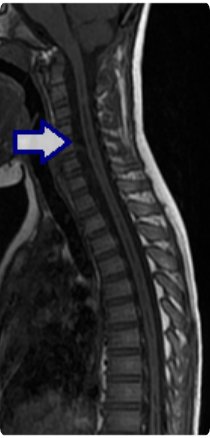

キアリ奇形、脊髄空洞症(せきずいくうどうしょう)

後頭部の頭蓋骨の先天的な発達の問題で、キアリ奇形という病気が起こります。後頭部痛などの原因になったり、脊髄に水がたまる現象(脊髄空洞症)を引き起こしたりします。特に脊髄空洞症を呈する場合は、手足の運動や、しびれ、背骨の変形などの原因となるため、後頭部の減圧手術を行います。また減圧のみで改善が得られない場合、空洞とくも膜下腔にチューブを挿入するシャント手術を行うこともあります。

手術前

減圧手術後(脊髄空洞の縮小)